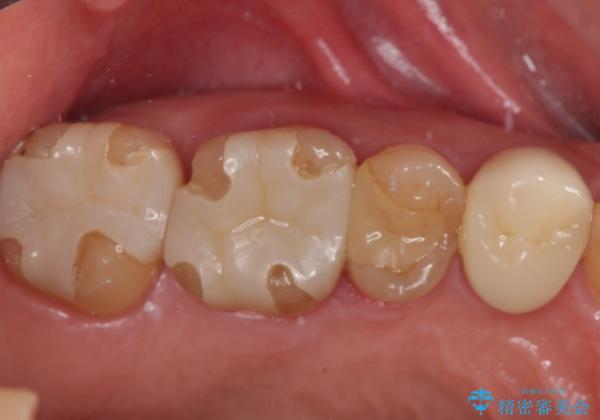

歯が欠けてしまった。オールセラミッククラウンによる補綴治療

- 食事中に歯が欠けてしまった事を主訴に来院された患者様です。

小臼歯が広範囲に欠けてしまっています。

部分的な詰め物では再びかけてしまうリスクが高いため、オールセラミッククランにて補綴治療をすることとしました。